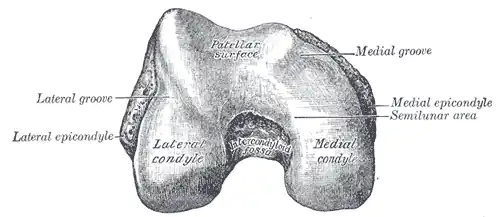

Lower extremity of right femur viewed from below. | |

The lateral condyle is one of the two projections on the lower extremity of the femur. The other one is the medial condyle. The lateral condyle is the more prominent and is broader both in its front-to-back and transverse diameters.